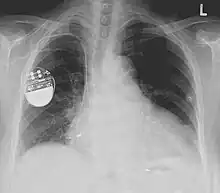

Une incision est faite en dessous d'une des deux clavicules après une anesthésie locale[19]. La ou les sondes sont introduites soit après dénudation d'une veine céphalique soit après ponction de la veine sous-clavière[20]. Elles sont poussées dans le réseau veineux et la progression de leur extrémité est suivie par un appareil de scopie. Elles sont placées dans leur cavité cardiaque respective. La sonde ventriculaire droite est positionnée traditionnellement à la pointe de ce dernier. Elle peut être placée également au niveau du septum (paroi séparant les deux ventricules), ou près de l'issue vers l'artère pulmonaire (« chambre de chasse »)[21]. La sonde auriculaire est positionnée soit dans l'auricule (petit cul-de-sac permettant une bonne immobilisation), soit dans la paroi latérale droite[14]. Le bon positionnement est vérifié par la scopie et par la mesure du seuil de stimulation (énergie électrique minimale transmise à la sonde et provoquant une contraction du muscle de la cavité), du seuil de détection (mesure par un voltmètre de l'activité électrique du cœur par l'intermédiaire de cette sonde) et de l'impédance de la sonde.

Les sondes sont alors reliées au boîtier qui est introduit dans une poche confectionnée sous la peau dans la région sous-claviculaire, ou sous le muscle pectoral[22]. La peau est ensuite suturée.

Une radiographie pulmonaire est faite de manière usuelle, après l'intervention, afin de vérifier l'absence de pneumothorax (accident possible en cas de ponction de la veine sous-clavière) et le positionnement des sondes[14].